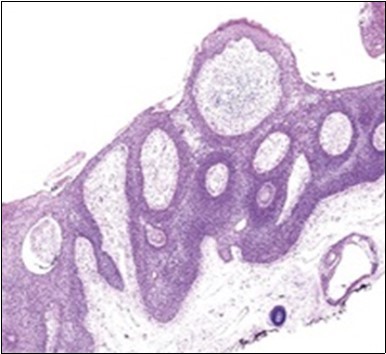

Figure 2.Epidermal projections lined with atypical and malignant epithelial cells in eccrine porocarcinoma (14).

Epidermal projections lined with atypical and malignant epithelial cells in eccrine porocarcinoma (14).